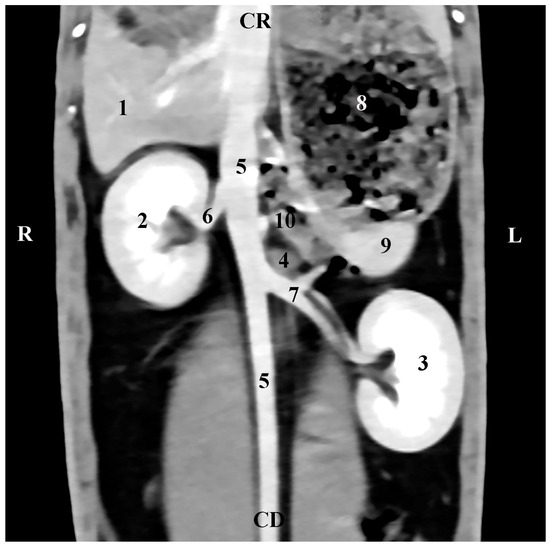

The dorsal (coronal) post-contrast anatomical CT study of regio abdominis through the dorsal plane 30 mm ventrally to the spine showed the elliptical shape of the homogeneous and sharply delineated image of the right adrenal gland. The gl. adrenalis dextra was located in the regio abdominis lateralis dextra of the regio abdominis media. The gland was retroperitoneally located, medially in contact with the v. cava caudalis, and was observed craniomedially to the hyperattenuated borders of the right kidney and caudally to the Proc. caudatus of the caudate liver lobe, with which it was in anatomical contact. The border between them was defined by hypoattenuated contours of the impression of the right adrenal on the proc. caudatus. Dorsally, the gland was in contact with the m. longissimus (Figure 5).

Figure 5. Dorsal (coronal) CT post-contrast anatomical study of the rabbit abdomen (at the plane 30 mm ventral from the vertebral column). CR—cranial; CD—caudal; R—right; L—left. (black star) right adrenal gland; (1) Right kidney; (2) left kidney; (3) right adrenal gland; (4) liver; (5) fundus et corpus ventriculi; (6) v. cava caudalis; (7) aorta abdominalis; (8) longissimus muscle; (9) impression of the right adrenal gland; (*) proc. caudatus.